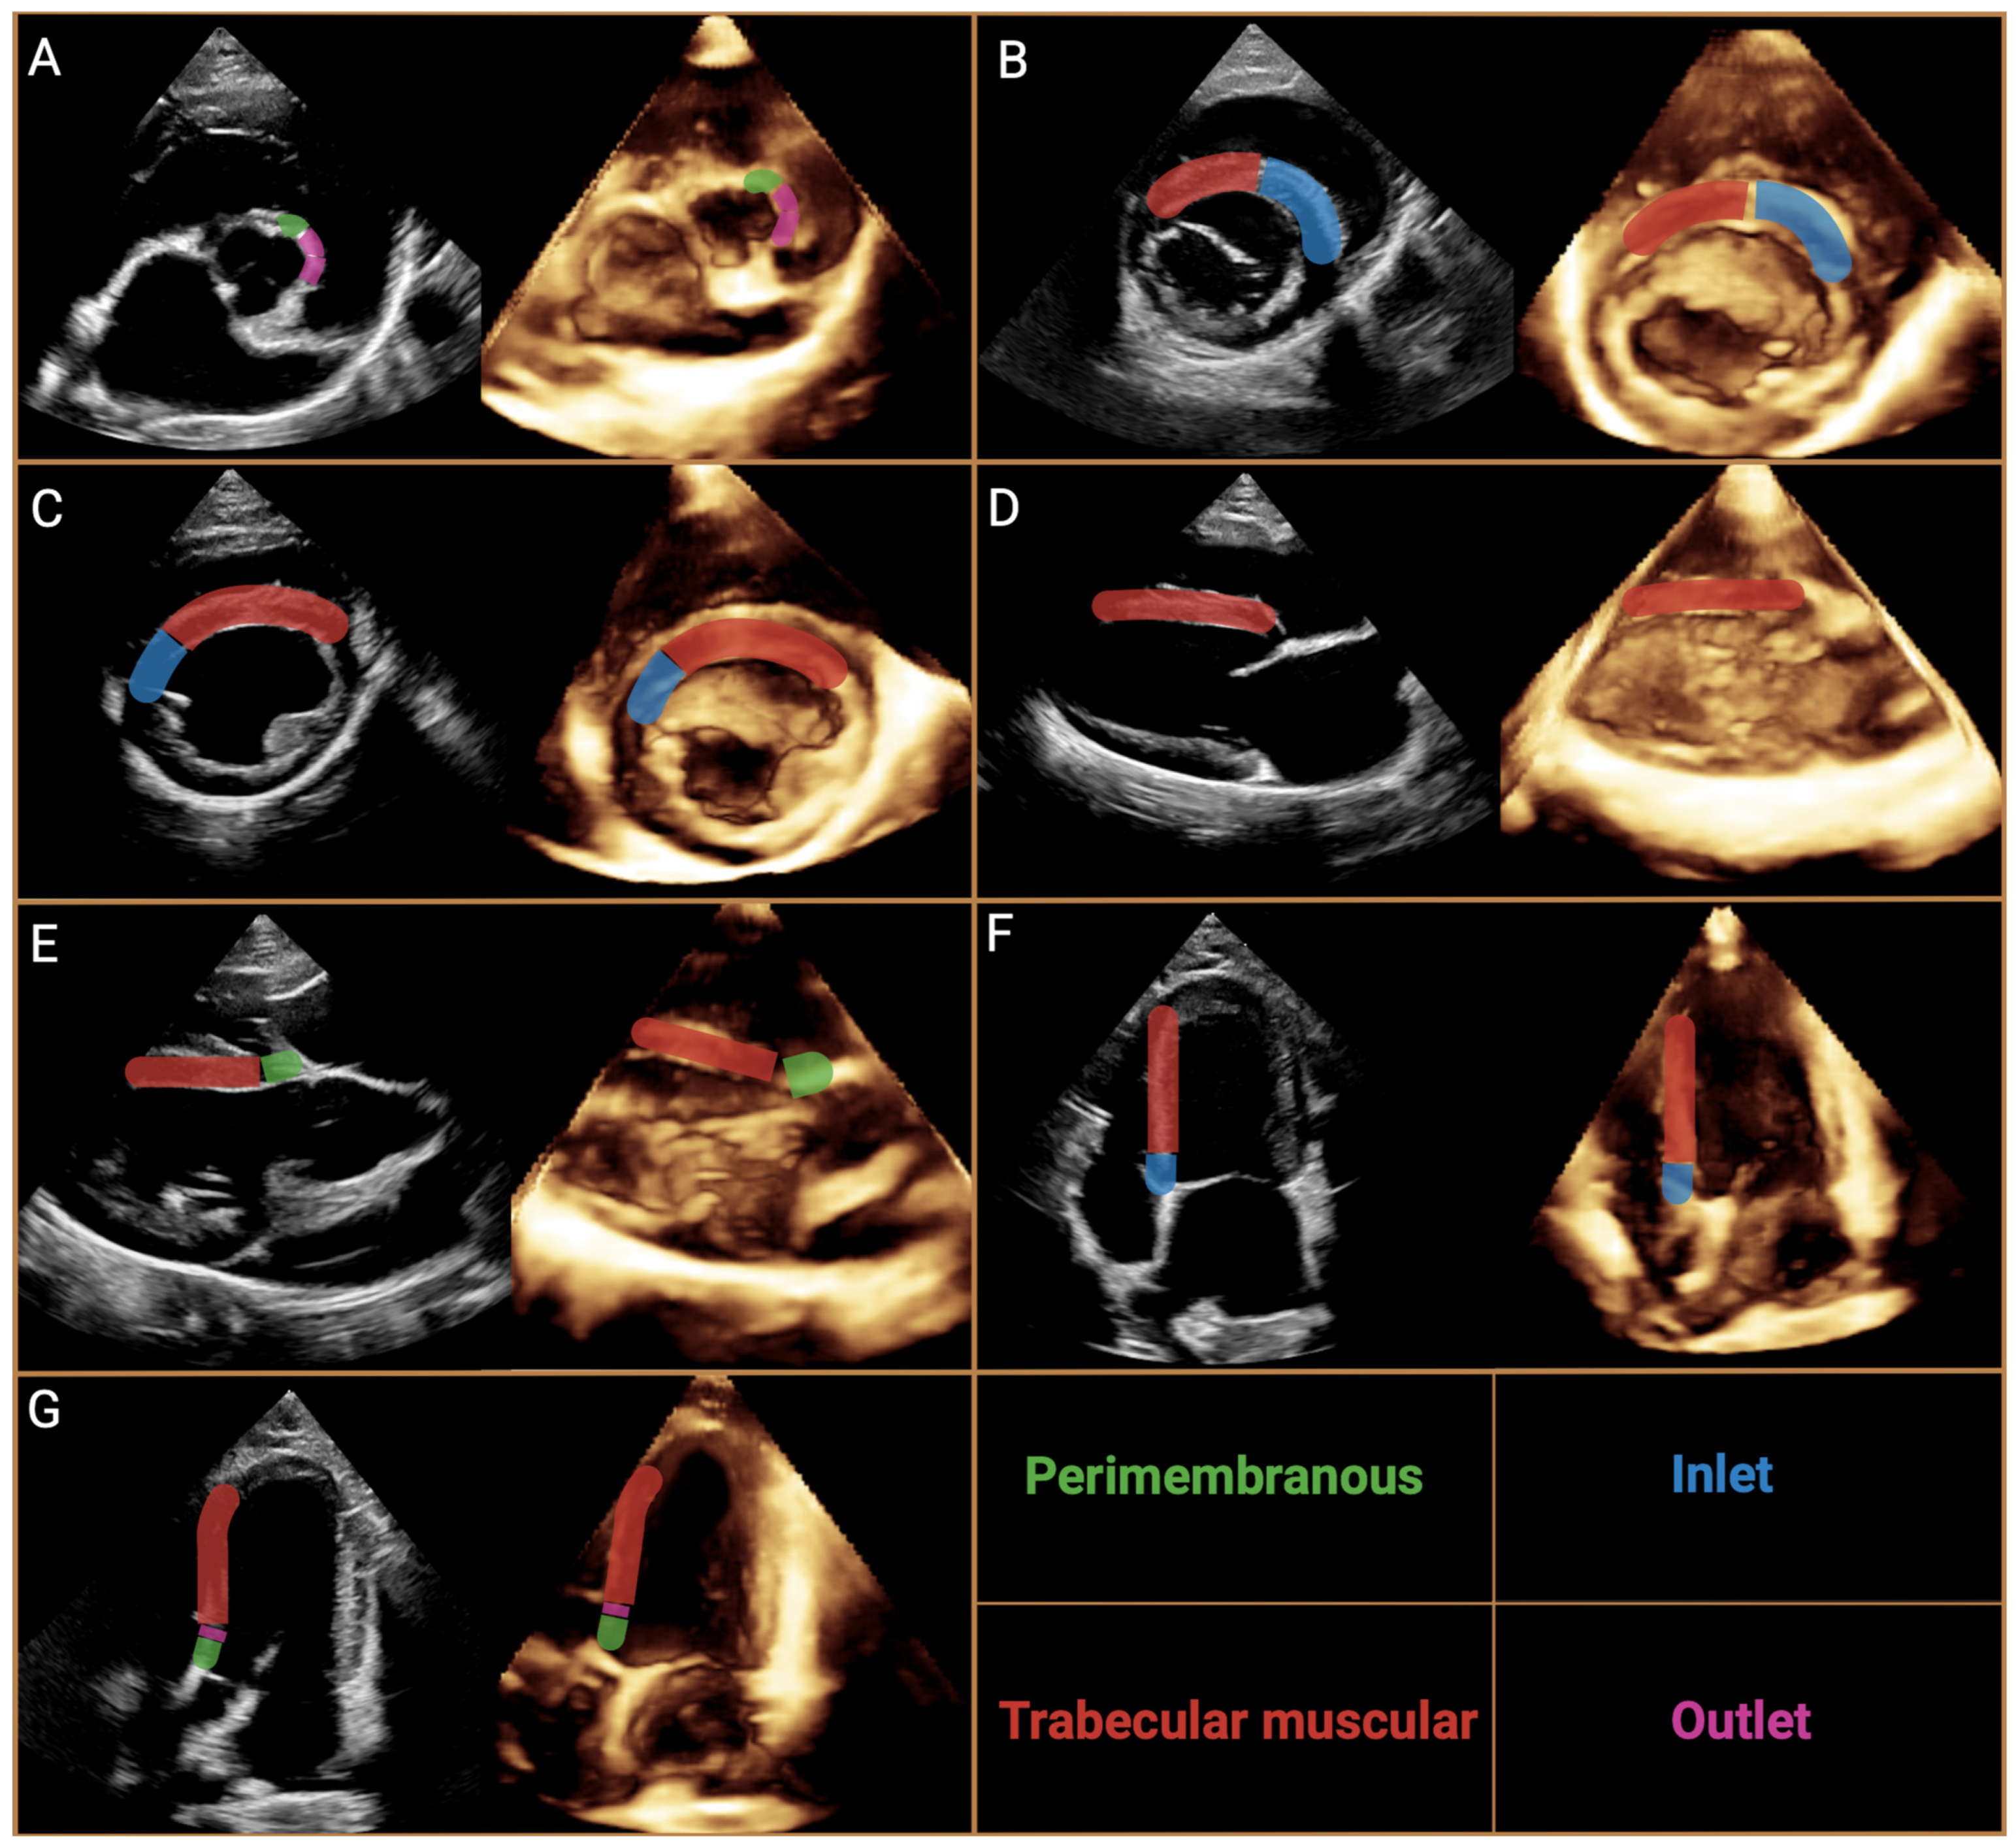

Figure 3.

Cross-section of the heart as seen from the right atrium and right ventricle with the most important topographic structures. The cross-section of the right ventricle shows all the subtypes of defects according to The International Society for Nomenclature of Paediatric and Congenital Heart Disease Nomenclature with the most common phenotypes. A—central perimembranous ventricular septal defect, B—inlet ventricular septal defect with common atrioventricular junction, where the inferior rim of the defect has partially muscular borders, C—outlet ventricular septal defect between the limbs of the septal band (the dashed line indicates the border of the defect with this phenotype), C’—doubly committed, juxtaarterial outlet ventricular septal defect; defect located between the limbs of the septal band, but superior to the previous one, disrupting the fibrous continuity between the pulmonary artery and aortic valves. D, postero-inferior muscular defect; D’, midseptal muscular defect; D’’, apical muscular defect; D’’’, antero-superior muscular defect.

Despite extensive analysis, there were still some inconsistencies; therefore The International Society for Nomenclature of Paediatric and Congenital Heart Disease (ISNPCHD) established a new classification of VSDs that was accepted by the World Health Organization into the 11th iteration of the International Classification of Diseases. It focuses primarily on combining the previously mentioned strategies based not only on the exact location of the defect, but also on the structures bordering it, thus creating a common consensus. As a result, four main classes of VSD are listed: perimembranous central, inlet VSD with common AV junction, trabecular muscular, and outlet (Figure 3). In the terminology, each has subclasses that represent the phenotypes of the defect in question [4]. Central perimembranous defects are located below the posteroinferior limb of the septal band at the level of the anteroseptal commissure beneath the septal leaflet of the tricuspid valve on the right ventricular side. On the opposite side, they are located below the commissure between the right and noncoronary leaflet of the aortic valve. Inlet defects are located in the inflow portion of the RV below the anteroseptal commissure of the tricuspid valve, the posteroinferior limb of the septal band, and the medial papillary muscle. They may extend toward the membranous part of the interventricular septum and be associated with the overriding and straddling of the tricuspid valve and the malalignment of the atrial septum relative to the ventricle septum. Trabecular muscular defects are located in the apical part of the ventricle septum and have completely muscular borders. They are divided into midseptal, apical, postero-inferior and antero-superior muscular VSDs. Cases of multiple muscular VSD of the “Swiss cheese septum” type are also noted. The last type mentioned, outlet defects, represents the most complicated type of division due to the large number of possible phenotypes of occurrence concerning location and adjacent structures, as well as conduction pathways. They most commonly open into the RVOT between the anterosuperior and posterosuperior limb of the septal band. They can be associated with malalignment between the outflow septum and the apical part of the interventricular septum, by which further subclasses can be distinguished as outlet perimembranous defect, outlet muscular defect and doubly committed juxtaarterial defects with a muscular or fibrous posteroinferior rim [4]. However, a detailed explanation and description of each defect location with its visualization can be found in an announcement issued by ISNPCHD [4]. This subdivision allows a strategic approach to choosing the best possible surgical access and correction of the defect while minimizing the risk associated with severe arrhythmias [72]. We believe that standardizing the classification of VSD in veterinary cardiology will greatly improve communication between veterinary cardiology internists, but also contribute to an easier understanding of the location of VSD, and to determining the best strategy for patient management. Therefore, we fully recommend the incorporation of the classification established by ISNPCHD into veterinary medicine.